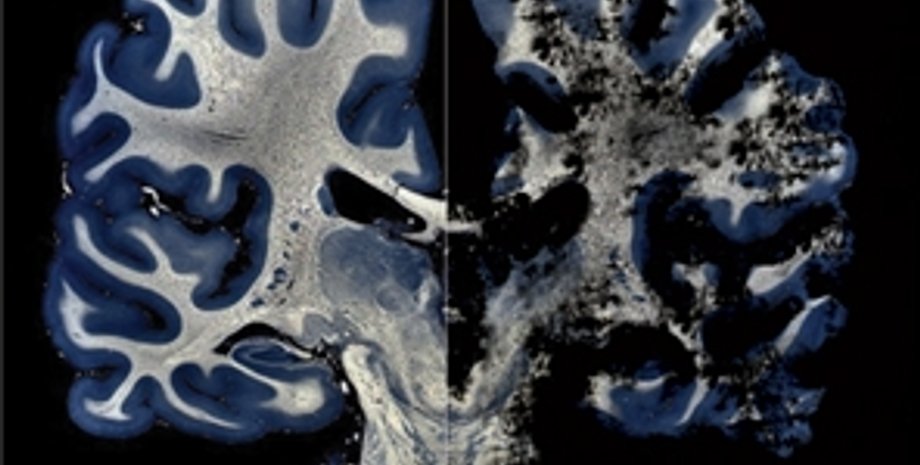

Морг. Патологоанатом вскрывает череп человека, который еще вчера был жив. Однако врачи так и не смогли с уверенностью поставить ему диагноз. В последнее время несчастный никого не узнавал, его голова и конечности непроизвольно тряслись. Посмертное исследование позволило установить: необратимые изменения в мозге больного вызвали прионы.

— Прионы, или патогенные белки, ведут к фатальным изменениям головного мозга, — рассказывает заведующий лабораторией биохимии Института отоларингологии АМН Украины им. Коломийченко, кандидат биологических наук Сергей Веревка. — Их открыл профессор неврологии, вирусологии и биохимии Калифорнийского университета Стенли Прузинер, за что получил в 1997-м Нобелевскую премию. Прионы вырабатываются клетками центральной нервной системы, то есть имеются абсолютно у всех млекопитающих, в том числе и у нас с вами. нормальные прионы могут мутировать в патологическую форму. Отличие ее от нормальной — в укладке белковой цепи. Две химически идентичные белковые молекулы в зависимости от способа скручивания "молекулярного клубка" ведут себя абсолютно по-разному — либо быстро расщепляются ферментами по выполнении своих функций, либо вызывают необратимую и ведущую к смерти деградацию клеток центральной нервной системы.

— Особенно плохо изучены наследственные прионные болезни, — отмечает Руфина Виноградова. — У них длительный скрытый период развития — около 20 лет. Человек может годами быть носителем прионной инфекции и не знать об этом. Обычно ее определяют уже после того, как он заболел, а то и умер.

Но как быть с донецкими трупами? Свидетельствуют ли они, что нам угрожает реальная, а не выдуманная опасность прионной болезни? Профессор Шлопов утверждает, что у умерших людей была обнаружена спорадическая (от греч. sporadikоs — единичный, отдельный) форма патогенных прионов, никак не связанная ни с инфицированным мясом, ни с переливанием крови. К тому же, отмечает ученый, прионы были найдены не одномоментно у нескольких покойников, а на протяжении нескольких лет.

— Первоначально причиной их смерти прионная болезнь не считалась, — объясняет г-Шлопов. — Истинный фактор выяснился, когда мы с коллегами ретроспективно изучали морфологические и клинические признаки их болезней. Разумеется, это наше исследование — сугубо научное. Смерти никак не связаны с употреблением в пищу инфицированного мяса или с переливанием крови.